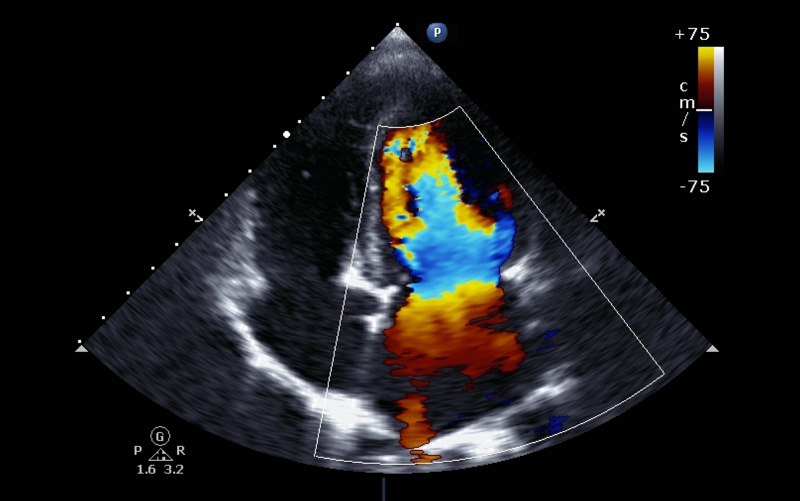

Tapping into the technology behind facial recognition programs and self-driving cars, researchers in a new study have taught computers key elements of assessing echocardiograms, potentially simplifying an otherwise extensive process now done by humans.

Researchers created algorithms to recognize images and potential heart problems that echocardiograms commonly capture, including enlarged chambers, diminished pumping function and even some uncommon diseases.

Echocardiograms help doctors evaluate heart function by using sound waves to create snapshots of every part of the organ. Because they don’t give off radiation and can be given easily in a medical office, they’re a popular imaging choice to diagnose heart disease. But, Dr. Rahul Deo, the study’s senior author, said they’re not done enough because the process of assessing results is long and taxing.